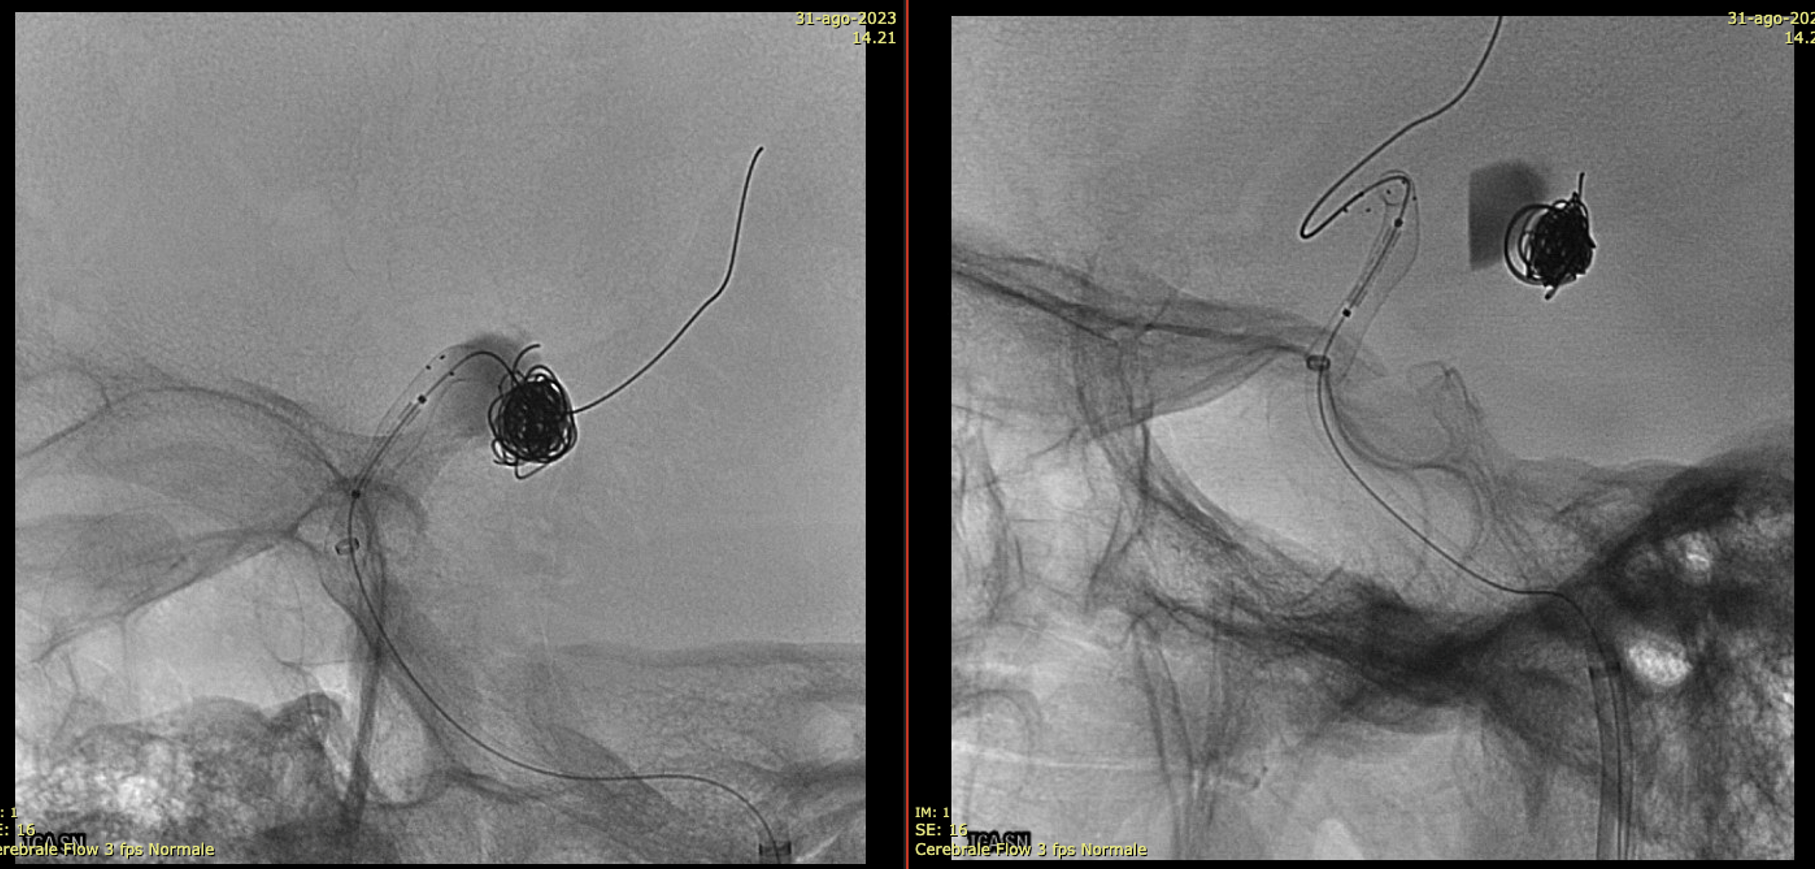

Noncontrast / dry Vaso-CT, 22 cm FOV 20 seconds acquisition, followed by a secondary reconstruction with 50% FOV and 5123 resolution; Thick MIP.

Two Lvis EVO have been used (in inverse Y or ? lambda shape). The first from the left PCom into the left SCA. The second from the left PCom into the right SCA. Another microcatheter in jailed in the aneurysm for the subsequent coiling.

There are no labels or arrows on any of the devices. If you are not sure what is going on, we suggest studying the images until you do.

Thick MIP reconstruction of a Vaso-CT acquired with manual injection of right vert and left ICA at the same time. Vaso-CT, 22 cm FOV 20 seconds acquisition, followed by a secondary reconstruction with 67% FOV and 5123 resolution; Thick MIP.

The procedure finished with coiling of the basilar tip around the stents and PTA of right SCA stent at the crossing of the other stent

Post Rx. The key to this procedure, other than sophisticated understanding of the problem and the materials to be used, is a consistently effective antiplatelet state. Doing this without IIbIIIa in the lab for example risks major disaster.

At the 8 months follow-up, after passing from DAPT to SAPT, the aneurysm became smaller, with corresponding clinical improvement.

This is a key point — the success of treatment in aneurysms of this type is judged by cross-sectional imaging, not angio. With aneurysm shrinkage a good angiogram is guaranteed, while there are many examples of good-looking angiograms with moribund patients.